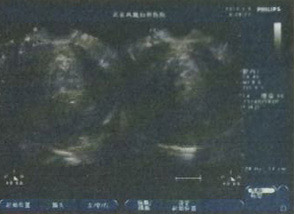

- 彩超及子宫输卵管造影发现其子宫内 8.2cm*6.8cm巨大肌瘤

德国WOLF宫腹腔镜检查

发现“8.2cm*6.8cm”巨大肌瘤

发现“8.2cm*6.8cm”巨大肌瘤

董长江教授耐心接待并做了详细检查,彩超、子宫输卵管造影及宫腹腔镜检查,发现其子宫内8.2cm*6.8cm巨大肌瘤,被确认为:宫内低回声子宫肌瘤。

- 专业彩超及宫腹腔镜检查发现巨大肌瘤